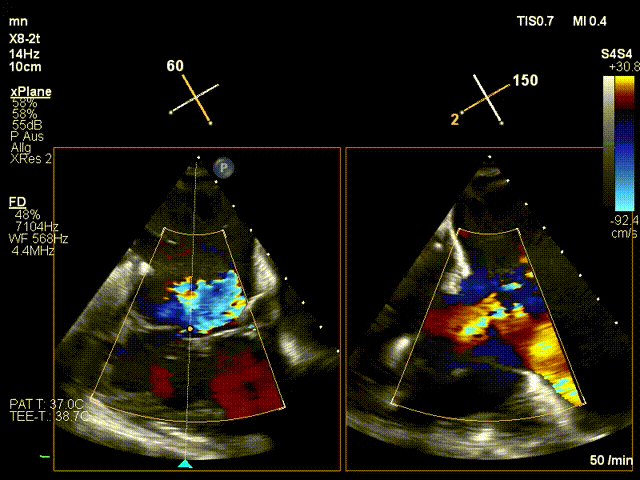

手術(shù)在全麻狀態(tài)下進(jìn)行。在加拿大圣保羅醫(yī)院的Anson Cheung教授的指導(dǎo)參與下,術(shù)者采用經(jīng)右側(cè)頸靜脈入路的方式將輸送器送入患者心臟內(nèi),在TEE及DSA引導(dǎo)下調(diào)整輸送器頭端角度,使得輸送器與三尖瓣瓣環(huán)平面垂直。在輸送器進(jìn)入右心室后釋放室間隔錨定裝置,而后釋放瓣葉夾持件(2個(gè)耳片結(jié)構(gòu))成垂直狀態(tài)。在TEE及DSA確定夾持件固定至三尖瓣葉根部且位于右室側(cè)后釋放人工瓣心房側(cè)盤(pán)片。隨后調(diào)整瓣膜同軸性以及室間隔錨定件位置(貼合室間隔),前推藏針管并固定,進(jìn)而釋放室間隔錨定裝置,并再次確認(rèn)瓣膜位置、穩(wěn)定性及同軸性,合攏輸送鞘后撤出輸送器,完成LuX-Valve Plus人工三尖瓣瓣膜的植入。

LuX-Valve Plus經(jīng)血管三尖瓣置換系統(tǒng)本次“出海”圓滿完成,術(shù)后Jörg Hausleiter教授對(duì)LuX-Valve Plus經(jīng)血管三尖瓣置換系統(tǒng)的器械性能和治療效果大為稱贊,認(rèn)為L(zhǎng)uX-Valve Plus的手術(shù)體驗(yàn)非常好。術(shù)后即刻超聲顯示三尖瓣反流消失,血流動(dòng)力學(xué)改善顯著,患者恢復(fù)快。Anson Cheung教授也肯定了LuX-Valve Plus術(shù)中操作的便捷性,認(rèn)為L(zhǎng)uX-Valve Plus容錯(cuò)率高,對(duì)術(shù)中影像的依賴較小,后期希望可以更多的應(yīng)用LuX-Valve Plus三尖瓣置換系統(tǒng)于臨床實(shí)踐,讓更多的三尖瓣重度反流患者盡早獲益,改善預(yù)后。